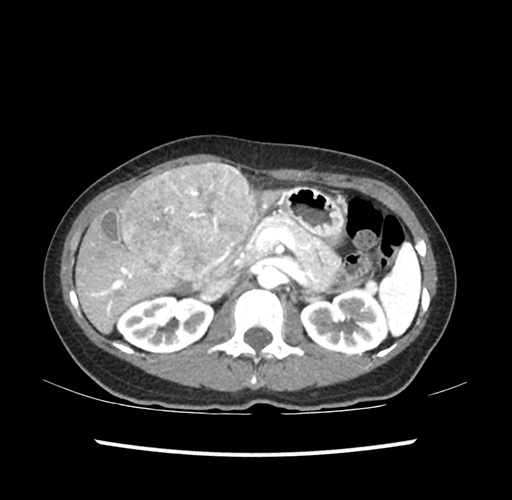

Imaging Analysis

Look through the patient's CT scan to identify any areas of concern for the necessary procedure.

Based on your CT findings, which issue(s) would give reason for "planned slowing down moment(s)" in this case?